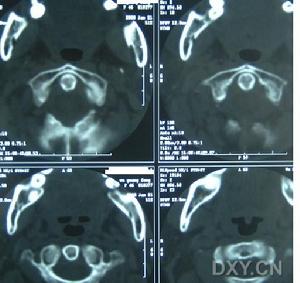

痙攣性斜頸本病的病因尚不明確,患者可能有家族史,少數繼發於腦炎、多發性硬化、一氧化碳中毒後,但大多無明顯病因。對其致病原因,有中樞性及外周性兩種推測。中樞性病因可能是額頂部皮質萎縮(Karte等,1981)、中腦被蓋部損害(Foez)、或因由間質核到丘腦系統(Hassler)或基底節等處病變(Cassirer,Foester,Firnforsch)所引起。也有人認為與遞質有關。5-羥色胺濃度降低可引起頭頸部鏇轉,兒茶酚胺濃度降低則可引起頭頸強直性偏斜等。Treckmann(1981)根據Jennetta理論,認為周圍性病因可能是微血管對副神經的壓迫,即副神經受血管長期壓迫產生局部脫髓鞘變,使離心和向心纖維之間產生短路,致異常衝動積累而產生頭部肌肉收縮,但目前未被公認。

2、病理機制

痙攣性斜頸的確切病理機制尚未明確,可能與以下幾方面相關:

痙攣性斜頸1)遺傳因素:部分成人肌張力障礙局限型發作是由遺傳決定的。

2)外傷:外傷一直被認為是痙攣性斜頸的病因,文獻報導9%-16%的病人既往有頭部或頸部外傷史,通常發生在發病之前的數周至數月。

3)前庭功能異常:有報導痙攣性斜頸病人的前庭-眼反射反應性增高或不對稱,在用肉毒素治療後不能糾正。前庭異常並非屬於原發異常,其他類型的局限性肌張力障礙(如:書寫痙攣,瞼痙攣)也可與痙攣性斜頸伴發。耳聾、眩暈和共濟失調不屬於痙攣性斜頸的特徵。同時,許多患者沒有前庭反射異常,而有較長時間痙攣性斜頸,這也許前庭異常繼發於痙攣性斜頸引起長期頭部姿勢異常。

4)其他:短時或長時間的頸部震動刺激發現,患者頭位改變存在明顯的差異,這是由於周圍本體感覺刺激發生改變,使中樞性控制頭頸代償扭轉調解功能受累,傳入神經衝動的中樞整合功能發生障礙。